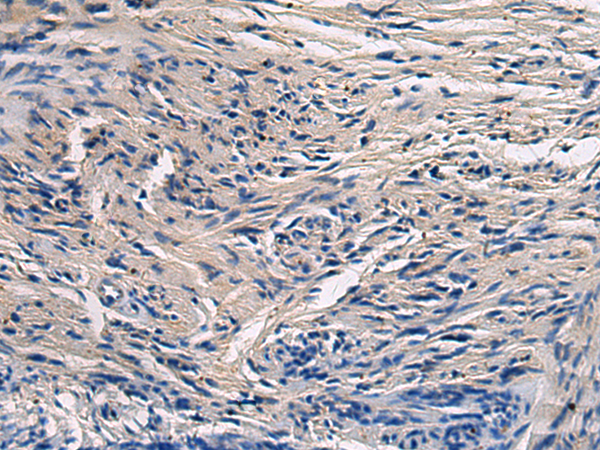

ELISA, IHC |

IHC positive control: |

Human esophagus cancer and Human brain |

IHC Recommend dilution: |

50-100 |